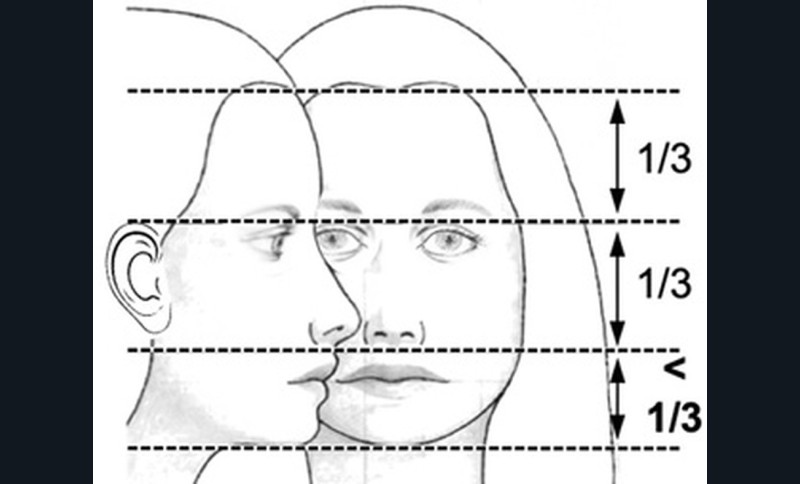

L’examen clinique orthodontique débute par un examen exobuccal de face et de profil qui permet à l’orthodontiste d’identifier certains signes d’appel du Sahos [4]. L’examen de face apprécie la forme globale du visage, la typologie et la symétrie faciale (fig. 5). Des signes caractéristiques sont souvent rapportés chez les enfants suspectés de Sahos : incompétence labiale au repos, hypotonie de la lèvre supérieure avec un angle naso-labial augmenté, visage allongé, orifices narinaires étroits et pincés et présence de cernes (fig. 6a) [5]. Ce sont des indicateurs indirects d’une obstruction ou d’un rétrécissement nasal et d’une ventilation buccale [5-6].

L’examen de profil apprécie les rapports maxillo-mandibulaires et la convexité du visage dans le sens antéropostérieur. Chez les enfants apnéiques, on note généralement la présence d’un profil convexe rétrusif avec un menton en retrait, associé à des dépôts graisseux si l’enfant est en surpoids. Une hypotonie de la lèvre supérieure, qui se traduit par un angle naso-labial ouvert, signe d’un hypo-développement maxillaire, est souvent présente [7]. Enfin, on observe parfois une contraction du muscle mentonnier associée à une occlusion labiale forcée (fig. 6b).